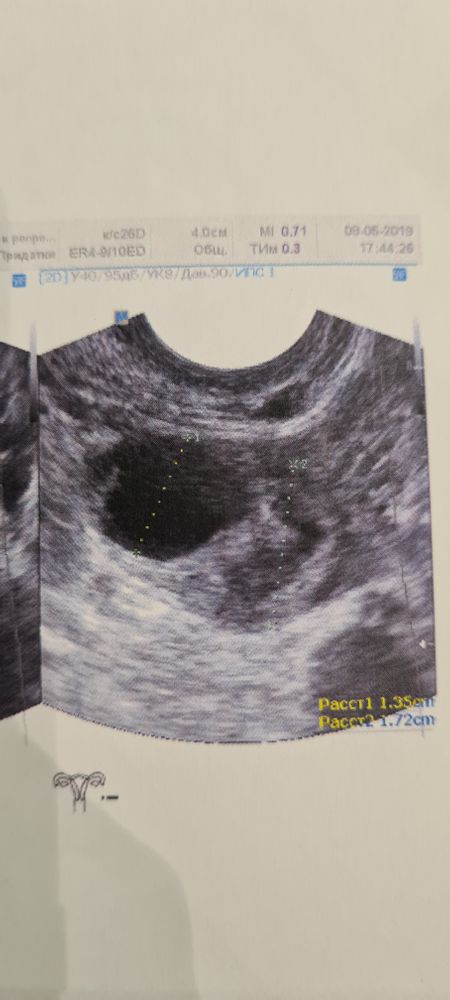

Ксюша, как по мне - они идентичны у вас на фото и это оба фолликулы, фолликул на узи имеет чёткие границы и внутри как бы чёрное пространство. 5 лет стажа планирования и моя любимая узистка мне показывала и рассказывала как и что)) у меня качество не такое хорошее, но вот на одном фото фолликул 13 мм и жёлтое тело 17мм, жёлтое тело совсем другой консистенции